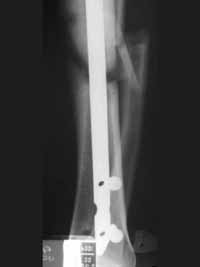

Las lesiones asociadas se presentaron en siete pacientes. Cinco en el grupo de pacientes que recibieron los clavos no fresados: fractura de húmero, fractura de maléolo posterior ipsilateral, fractura de pelvis estable, fractura del maléolo medial ipsilateral y una fractura de fémur ipsilateral (Figura 1).

Figura 1. Fractura ipsilateral de la diáfisis femoral, manejada con sistema UFN insertado de manera retrógrada.